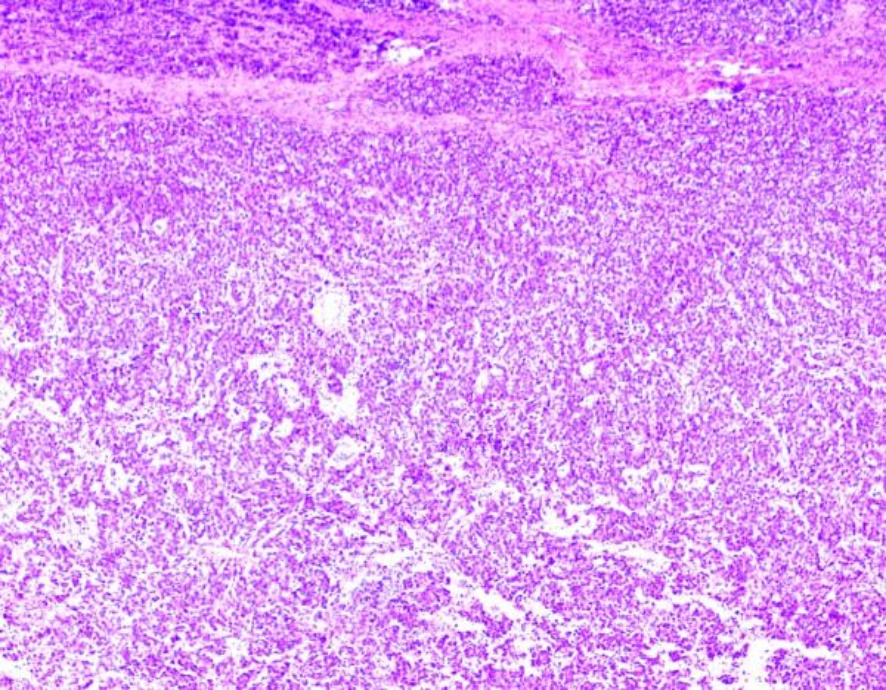

Figure 2. Postoperative pathological image of ovary with HE staining

2. 术后卵巢病理图HE染色

经科室病案讨论分析,患者于2024年5月17日行剖腹探查术,探查见盆腔无粘连形成,可见淡黄色积液约200 ml,盆腔包块巨大、来自左侧卵巢、上缘达剑突、两侧达腋中线、多房、实性、触似橡皮感、灰白色,表面未见破口、左侧输卵管水肿、子宫大小尚可、右侧卵巢亦实性增大如拳头大小、表面光滑、灰白色、右侧输卵管外观未见明显异常,网膜、腹膜、肠管、肝脏、胃表面未见结节,盆腹腔未扪及肿大淋巴结,行左侧附件切除 + 右侧卵巢囊肿剥除术,手术切除左侧附件重量4.3 kg,右侧卵巢肿瘤大小约6 * 5 * 4 cm,待快速冰冻病理回报提示双侧均考虑卵巢无性细胞瘤,(腹水):镜下见淋巴细胞、中性粒细胞、增生间皮细胞及异型细胞。病情告知家属,征求其意愿行保留生育功能手术及腹腔留管备热灌注化疗。术后诊断双侧卵巢无性细胞瘤。5月20日顺铂方案腹腔热灌注化疗。分别于6月18日、7月9日、8月5日、9月2日给予依托泊苷 + 顺铂(EP)辅助化疗同时注射亮丙瑞林去势保护卵巢功能治疗,共化疗4周期,术后复查各项肿瘤标志物及各项辅助检查均未见异常,已随访17个月,患者目前生存状况良好,按照卵巢恶性肿瘤随访提示长期随访中。